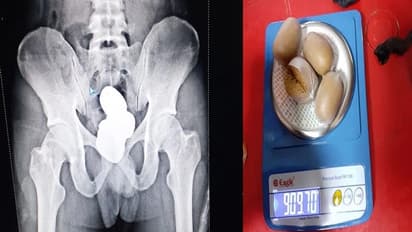

సోమవారం Imphal Airportలో ఓ ప్రయాణికుడి దగ్గర 900 గ్రాముల బరువున్న.. సుమారు రూ. 42 లక్షల విలువ చేసే బంగారు పేస్ట్ను సెంట్రల్ ఇండస్ట్రియల్ సెక్యూరిటీ ఫోర్స్ (CISF)స్వాధీనం చేసుకున్నట్లు ఒక ప్రకటనలో తెలిపింది. 909.68 గ్రాముల బరువున్న నాలుగు మెటల్ పేస్ట్ ప్యాకెట్లను అతని నుంచి స్వాధీనం చేసుకున్నారు.

CISF సబ్-ఇన్స్పెక్టర్ బి దిల్లీ దీని గురించి చెబుతూ.. ఒక ప్రయాణికుడిని పరీక్షిస్తున్నప్పుడు అతని మల కుహరం లోపల మెటల్ ఉండటం గమనించారు.. దీంతో వెంటనే అతన్ని గట్టిగా ప్రశ్నించగా.. విషయం బయట పడింది. అతని మల కుహరంలో 909.7 గ్రాముల బంగారాన్ని పేస్ట్ రూపంలో మార్చి నాలుగు ప్యాకెట్లలో దాచాడు.

దీంతో అతని నడుం కింది భాగాన్ని ఎక్స్-రే తీయడం కోసం అధికారులు అతడిని మెడికల్ టెస్ట్స్ రూం కి తీసుకెళ్లారు. ఆ ఎక్స్ రేలో తేలిన విషయం వారిని షాక్ కు గురి చేసింది.. ఎక్స్ రేలో అతని శరీరం లోపల లోహ వస్తువులు ఉన్నట్టు చూపించింది, దీంతో వారు మరింత గట్టిగా ప్రశ్నించడంతో ఆ ప్రయాణికుడు అసలు విషయం ఒప్పుకున్నాడని ఒక అధికారిక ప్రకటనలో తెలిపారు.